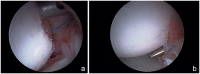

Results: The incidence of anterior shoulder instability events in the military occurs at an order of magnitude greater than in civilian populations, with rates as high as 3% per year among high-risk groups. With more than 90% risk of a Bankart lesion and high risk for instability recurrence, the military has advocated for early intervention of first-time shoulder instability while documenting up to 76% relative risk reduction versus nonoperative treatment. Preoperative evaluation with advanced radiographic imaging should be used to evaluate for attritional bone loss or "off-track" engaging defects to guide comprehensive surgical management. With complex recurrent shoulder instability and/or cases of clinically significant osseous lesions, potential options such as remplissage, anterior open capsular procedures, or bone augmentation procedures may be preferentially considered.